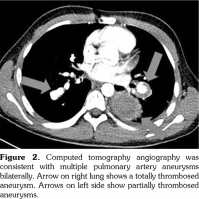

Chest X-ray showed retrocardiac hyperdensity on admission (Figure 1). Diagnostic investigations for tuberculosis were all negative. On bronchoscopy; left lower lobe bronchus was narrowed due to the external compression and abundant viscous secretions were observed. Computed tomography (CT) angiography was performed, which was consistent with multiple PAAs bilaterally (Figure 2). Diagnostic investigations such as echocardiogram and lower extremity venous Doppler ultrasonography, renal function evaluation, eye examination, abdominal ultrasound, and rheumatologic tests revealed no pathological findings. Our patient’s investigational tests for PAA were negative for cardiovascular disease, pulmonary hypertension or any infection.